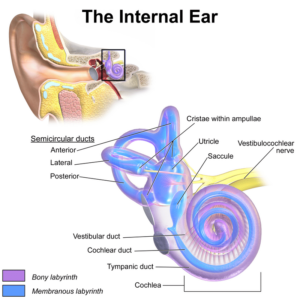

Acute Otitis Media (AOM)

Images

1